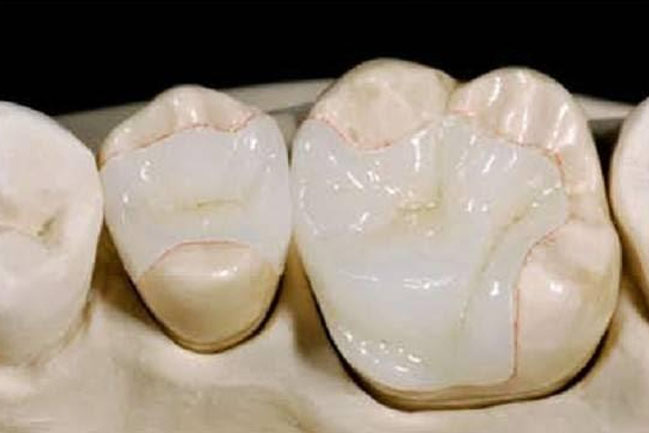

Inlays are used to replace fillings on a tooth’s biting surface. These are created in collaboration with your dentist and a laboratory. They are made of porcelain or gold and fit into the contour of the filling like a jigsaw puzzle piece.

Inlays are used to replace fillings on a tooth’s biting surface. These are created in collaboration with your dentist and a laboratory. They are made of porcelain or gold and fit into the contour of the filling like a jigsaw puzzle piece.